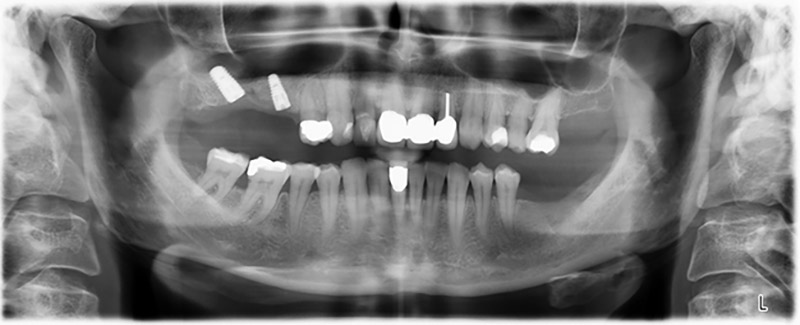

Image 20: Orthopantomogram after treatment